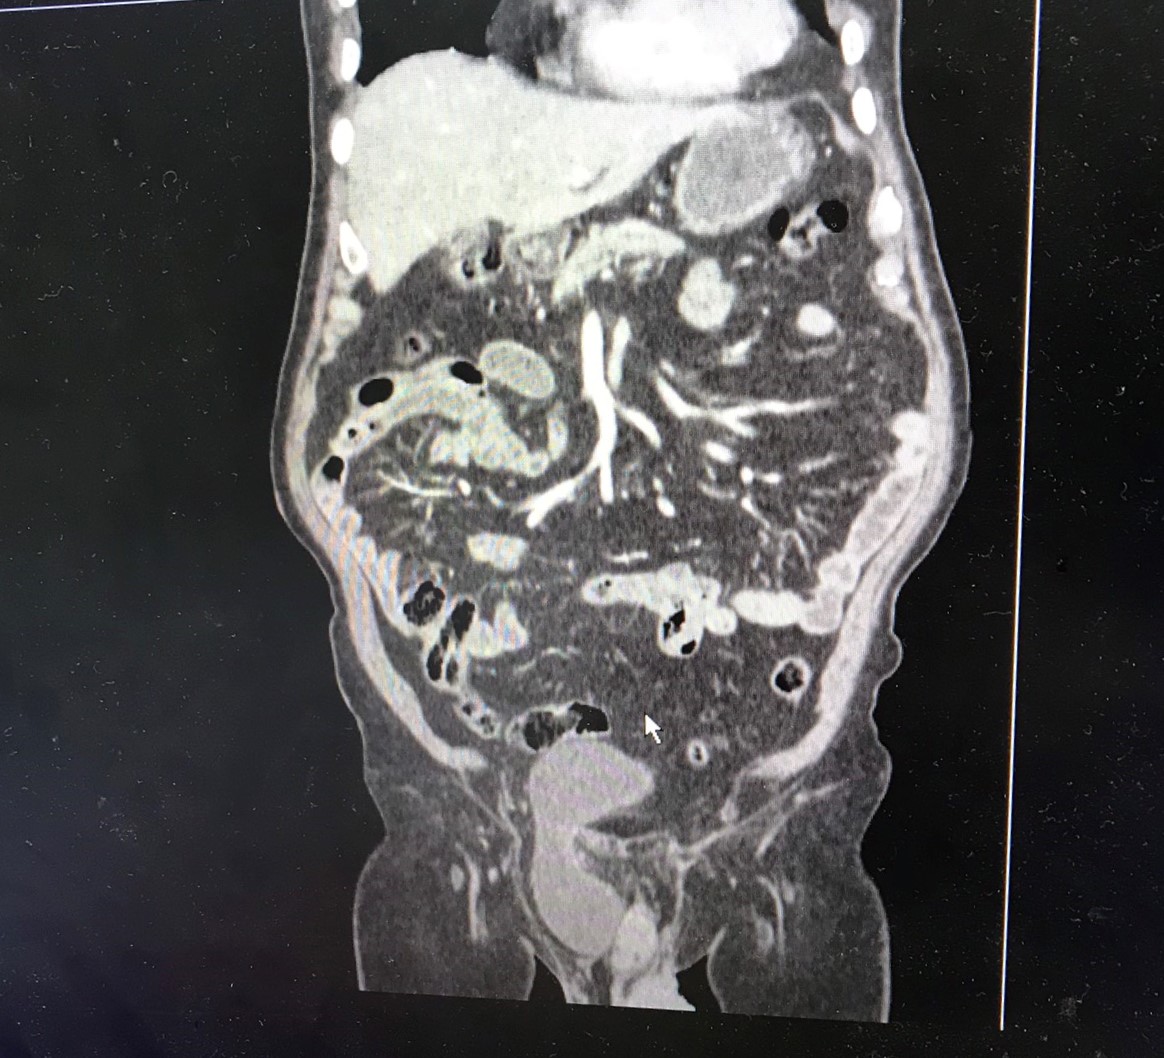

Bệnh nhân N.Đ.H, 84 tuổi, ở Hải An, Hải Phòng có tiền sử tăng huyết áp, đái tháo đường, rối loạn lipid máu, gan nhiễm mỡ độ 2, người bệnh có bụng béo mỡ, đã từng mổ thoát vị bẹn bên trái. Trước khi vào viện, người bệnh mắc rối loạn tiểu tiện, tiểu són, tiểu khó, tiểu không hết, có khối phồng to vùng bẹn phải và bìu phải, khối to dần và đau tức. Qua thăm khám, TS.BSNT Phạm Việt Hà – Giám đốc chuyên môn hệ Ngoại bệnh viện phát hiện khối của người bệnh lan xuống bìu, có dịch bên trong, cạnh tinh hoàn. Hình ảnh siêu âm và chụp cắt lớp vi tính cho thấy, hình ảnh thoát vị bẹn phải, nội dung bao thoát vị là một phần ruột non với một nửa bàng quang nằm trong bìu.